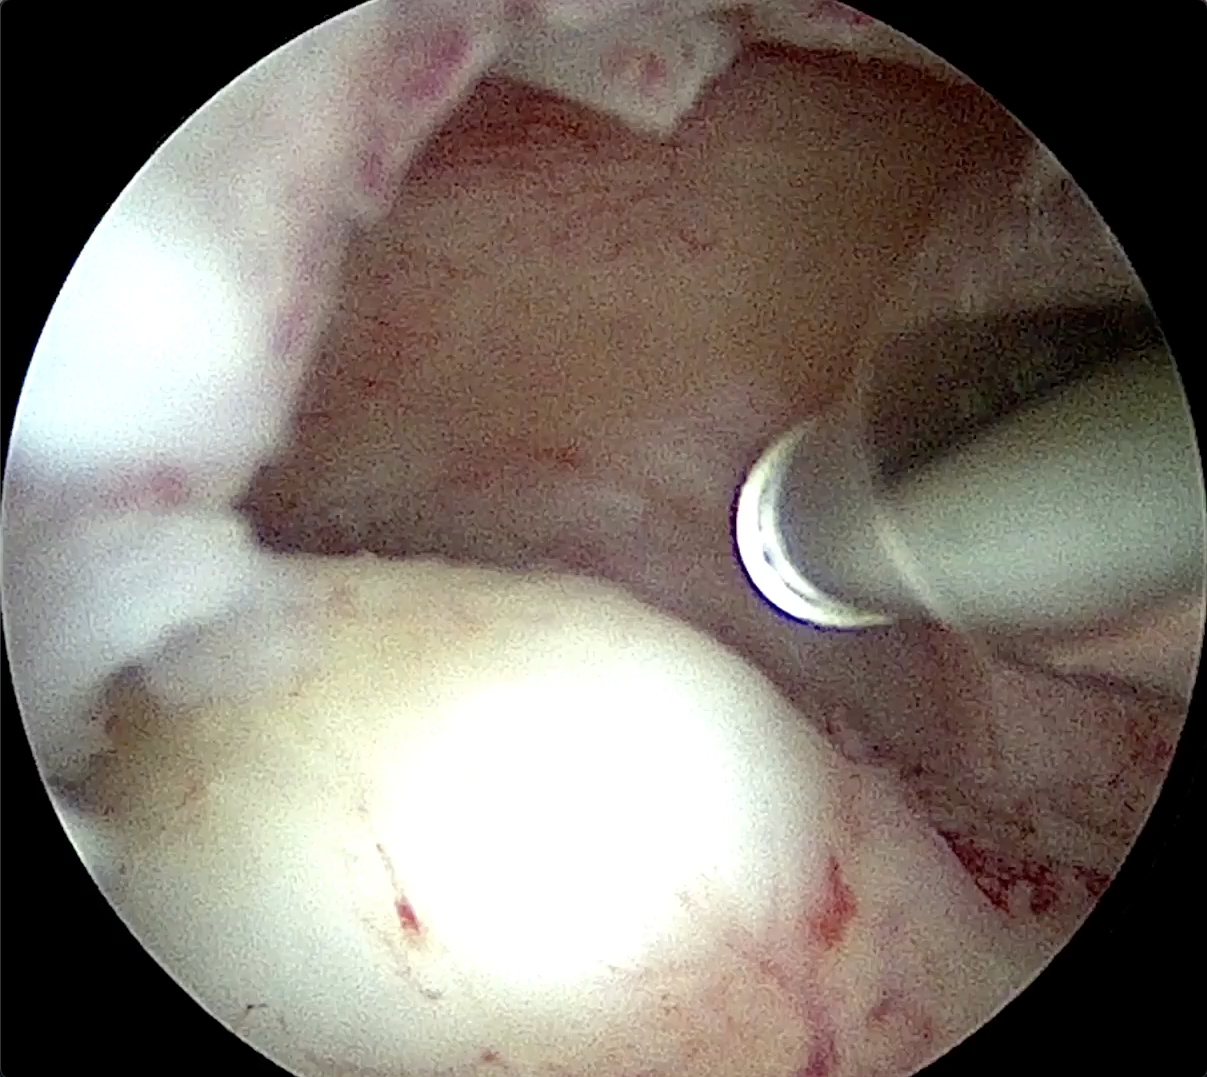

Hysteroscopic Myoma Removal with MyoSure device

This video shows the removal of an myoma using the MyoSure Reach device. The procedure is performed under direct hysteroscopic visualization in an office-based setting.

Myomectomy Resection 2cm

Watch how a myoma/fibroid can be removed with a Myosure device.

Removal of Fibroid with MyoSure XL Fibroid under local anaesthesia

This video shows a myomectomy, performed under local anaesthesia with Myosure XL.